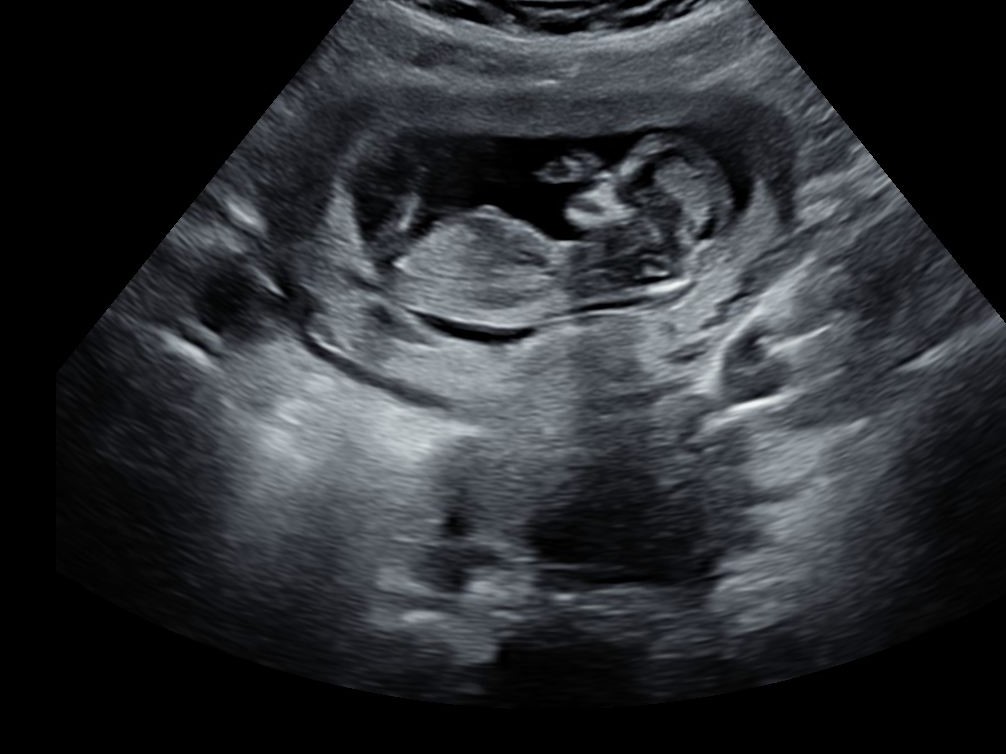

Today I had my 12 week scan. I already have 2 sons (8 and 9 years old) and we are hoping for a girl this time.

Tech couldn't see anything with the pottyshot, but is there a clue with NUB?

Attachment 38113

I'm not even sure I see a nub, sorry. I think *if* that's a little bit of the nub sticking out, I'd slightly lean boy since it looks angled. Again though, I'm not sure. Hopefully I'm wrong and it's a girl!